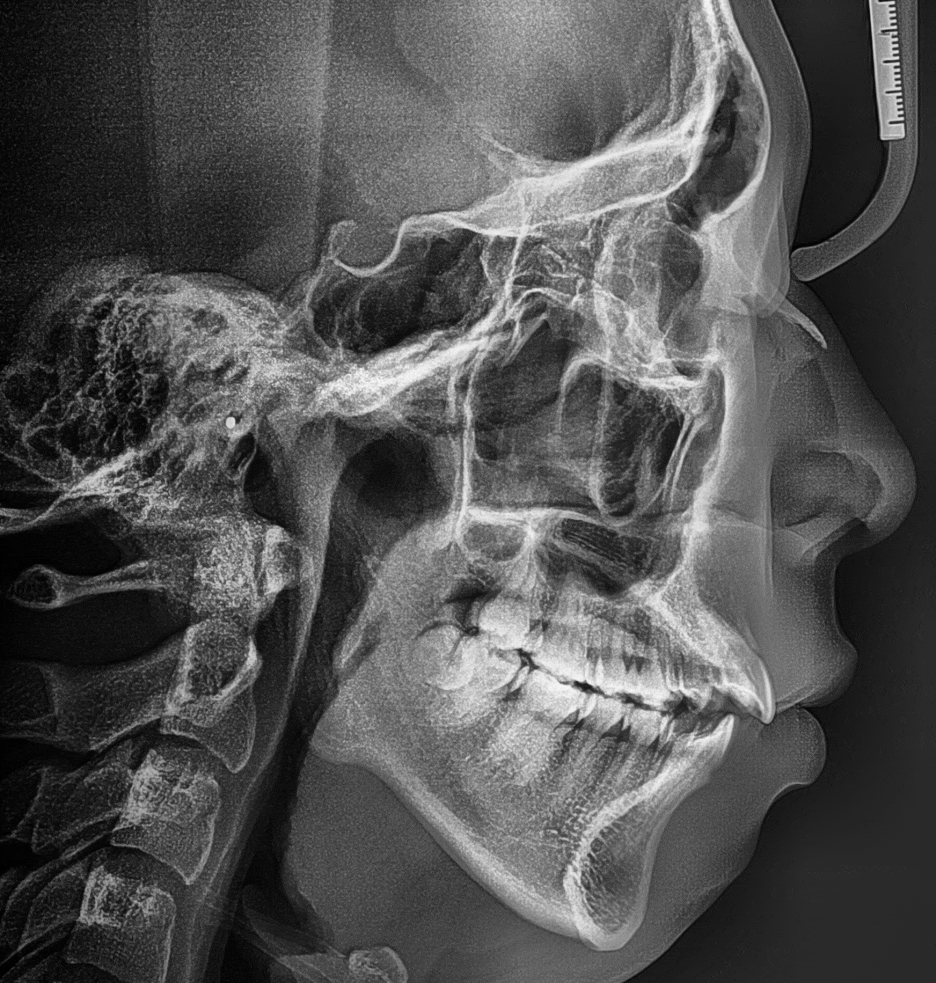

측면 두부방사선 사진 및 안모의 측면사진의

중첩 된 결과입니다.

사진을 보면, 턱이 거의 없는 무턱 증세를 띄고

있는 것이 한 눈에 보여집니다.

측면 두부방사선, 중첩 사진에 따른

전후 사진을 한번에 보여드립니다.